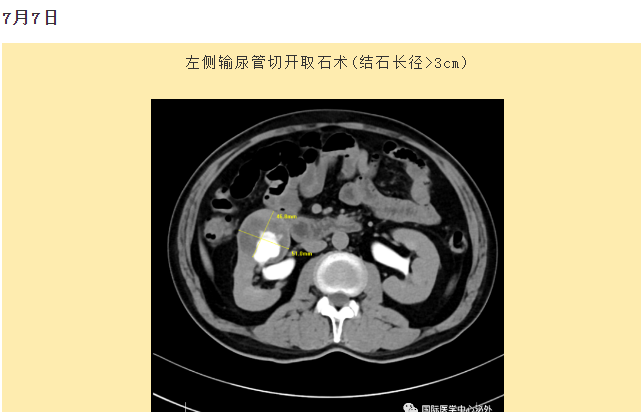

西安國際醫(yī)學中心醫(yī)院順利完成了達芬奇Xi(第四代)機器人裝機。7月6日—7月15日,泌尿外科成功完成了達芬奇Xi(第四代)機器人手術(shù)6例,標志著科室微創(chuàng)外科邁入新時代,造福萬千患者。